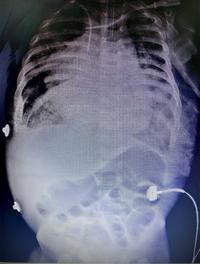

Une fois n’est pas coutume, pas d’énigme dans ce cas clinique mais la présentation d’un tableau de déformation rachidienne à savoir [...]